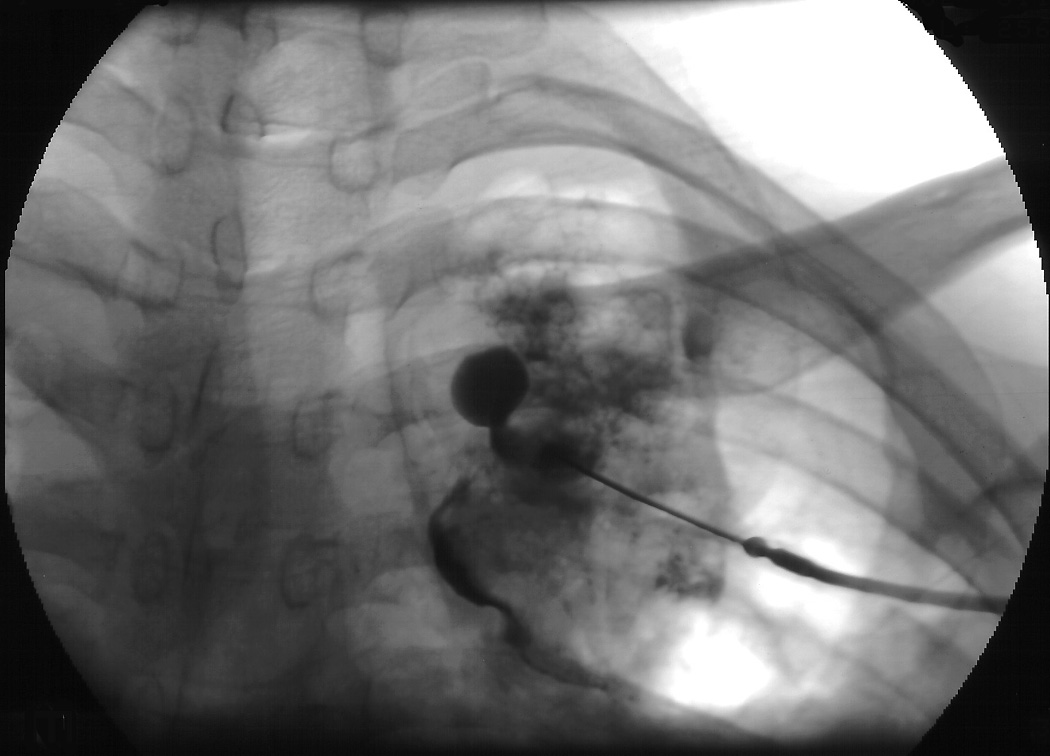

The definitive treatment of symptomatic aspergilloma is surgical resection. Patients with aspergilloma who present with hemoptysis are at risk of death due to massive hemoptysis and/or respiratory insufficiency caused by aspirated blood. Catheter embolization of bronchial arteries can be used to control acute bleeding (Figure 1), but is not durable. Likewise, intracavitary instillation of antifungal agents has mixed outcomes and seldom results in complete resolution of the cavity (Figure 2 ) 1. Systemic antifungal agents play little role as primary treatment because they do not penetrate the aspergilloma cavity 2. Resection in appropriate patients provides a definitive diagnosis and a durable treatment response.

| Figure 1: Catheter embolization of bronchial arteries | Figure 2: Intracavity instillation of antifungal agents |